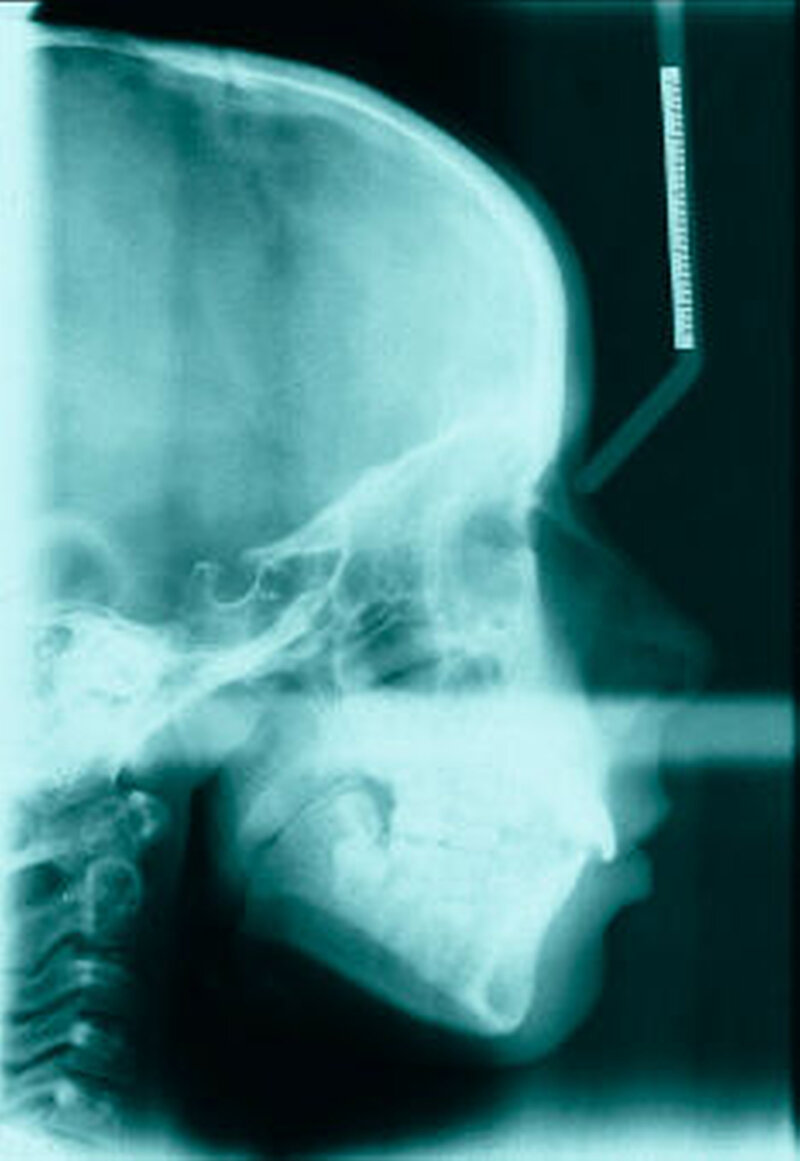

Bereits 2004 wies Carla Evans [Evans, 2005] auf das Risikomanagement bei Allgemeinerkrankungen hin und stellte am Beispiel der JIA dar, dass Unterkieferrücklagen und frontal offene Bisse aus der Kiefergelenkzerstörung entstehen können. Die Röntgenaufnahmen einer JIA-Patientin mit oligoartikulärer Form und Beteiligung des rechten Kiefergelenkes zeigen den typischen Verlauf sehr gut. Bei ursprünglich sehr dezenten Befunden, wie einer s-förmigen Mundöffnung von 44 mm, einer geringen Mittenabweichung um 2 mm nach rechts und einem frontal offenem Biss klagte sie über Schmerzen beim Essen, was den Anlass zur weiteren Diagnostik bot. Die erste Panoramaröntgenschichtaufnahme (Abbildung 1a-c) zeigt auf der rechten Seite einen abgeflachten Kondylus und eine bereits verstrichene Fossa condylaris. Ein Jahr später vermittelt das Fernröntgenseitenbild (Abbildung 1d) trotz fortschreitender kondylärer Resorption ein harmonisches Bild, während nach drei Jahren bei voranschreitendem Abbau des rechten Kondylus (Abbildung 1e) eine Rücklage der Mandibula und eine Bissöffnung manifest sind (Abbildung 1f).

Die Fernröntgenseitenaufnahme in Abbildung 2a zeigt ein „rheumatisches“ Profil mit retraler, hypoplastischer Mandibula, oft kombiniert mit einer Schwäche des M. masseter auf der betroffenen Seite. Der Funktionsschmerz erzeugt „Kaufaulheit“. Die Gesichtsasymmetrie (Abbildung 2b) betrifft meist Kinn, aufsteigenden Ast und die Höhe der Kieferwinkel. Auch die nicht dentoalveoläre Mittellinienverschiebung kann auf eine JIA hinweisen. Kreuzbisse variieren in Abhängigkeit vom Grad der Unterkiefermittenabweichung. Gemeinsame Auftreten eines frontal offenen Bisses und eines vergrößerten Overjet sind als klinische Anzeichen zu bewerten.